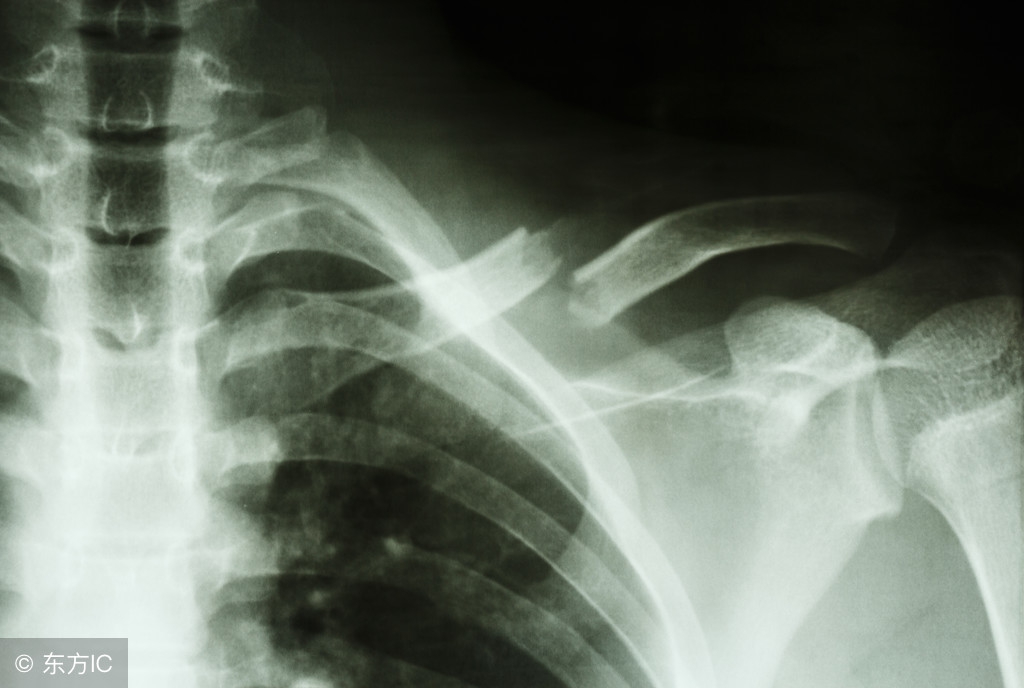

对于连枷胸这一情况,很多人可能比较陌生,这实际上是一种疾病名称,其指的是机体存在的严重的闭合性胸部损伤,最终导致其多根多处肋骨发生骨折的情况。一般来讲,严重纯性闭合性胸部创伤可能会造成机体两根或以上肋骨发生双处骨折的情况,最终使得其局部胸壁失去肋骨支称而发生软化的情况,与此同时,患者们还可能会出现有反常呼吸即吸气时软化区胸壁内陷,呼气时外突的情况,即为连枷胸。

胸部的肋骨骨折是发生率比较高的一种胸部损害,针对这类情况引起的连枷胸一般是需要特别注意的,尤其是后期的治疗。而且多处肋骨骨折是引起连枷胸的常见原因,这一般是外界的伤害造成的,很多人对于连枷胸和肋骨骨折的联系比较好奇,严格来说,单一的肋骨骨折并不是连枷胸,所以连枷胸一般是和骨折的肋骨数量也有关。而且严重钝性的闭合性胸部创伤也会因此多根肋骨骨折,从而引起连枷胸,由此可见连枷胸和肋骨骨折的情况也有关系,因此在治疗的时候就需要考虑这类因素了。